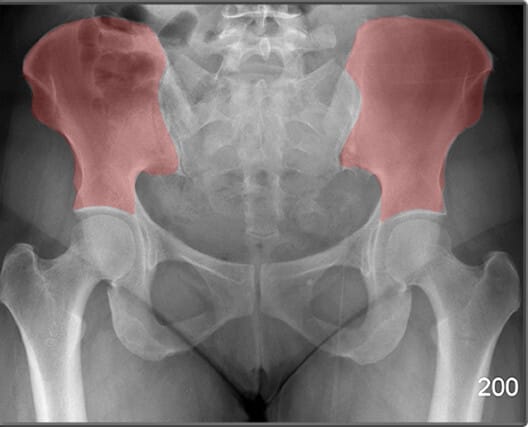

장골 (Ileum)

| 장골 (Ileum) |

| ✅ 골반의 상부를 구성하는 큰 뼈로, 장골능(iliac crest)과 전상장골극(ASIS) 등을 포함합니다. |

| 🔴 AP view에서는 넓은 곡선형 음영으로 관찰되며, 골반 골절 여부 평가에 중요합니다. |

장골능 (Iliac Crest)

| 장골능 (Iliac Crest) |

| ✅ 골반의 가장 상부 경계로, AP pelvis 영상에서 양측 상단에 대칭적으로 보입니다. |

| 🔴 곡선을 이루며, 체위 기준점으로도 활용됩니다. |

전상장골극 (ASIS, Anterior Superior Iliac Spine)

| 전상장골극 (ASIS, Anterior Superior Iliac Spine) |

| ✅ 장골의 앞쪽 윗부분에 돌출된 뼈로, AP view에서 골반의 가장 상전방에 대칭적으로 위치합니다. |

| 🔴 표면해부학에서 중요한 구조로 , 골반의 변위를 대략적으로 파악할 수 있습니다. |